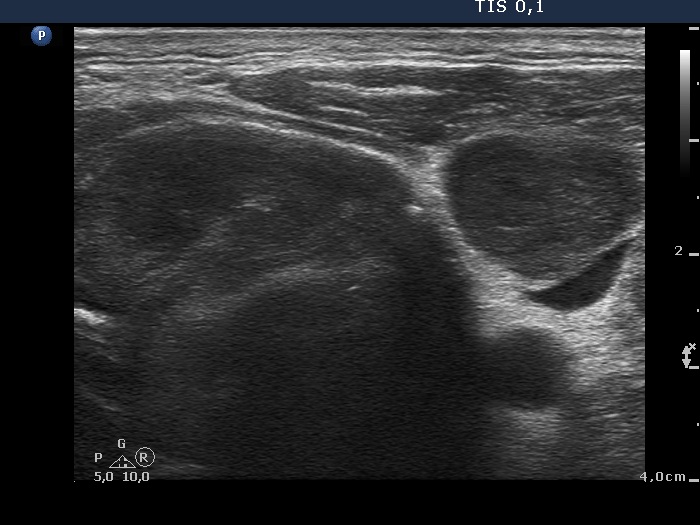

Ultrasonography revealed that the palpable mass contained the enlarged left thyroid composed of a large hypoechogenic nodule with irregular borders and multiple irregular lymph nodes in the left side of the neck.